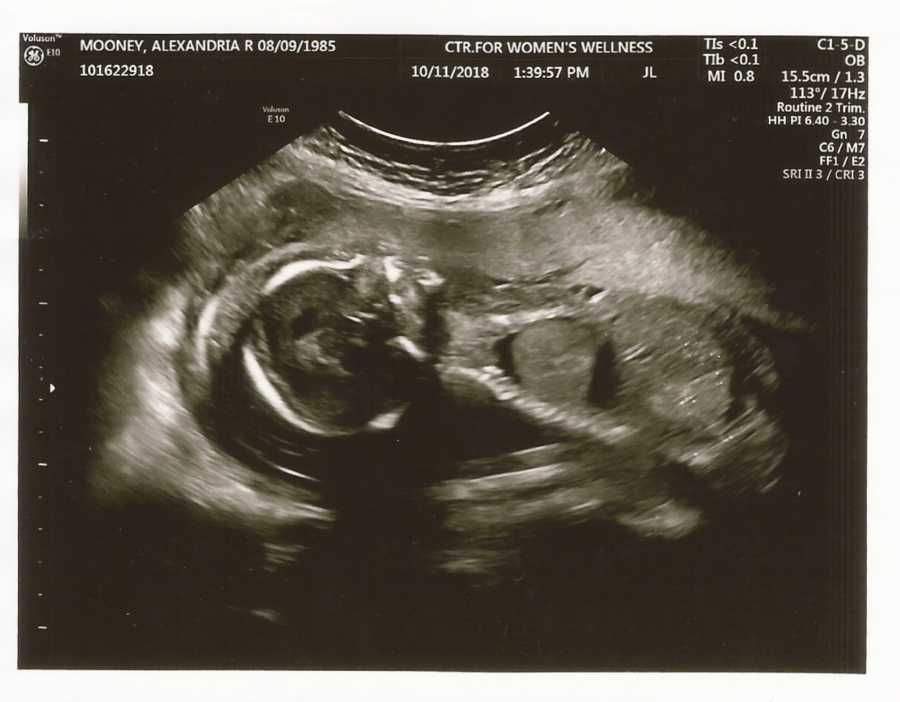

Then one night everything changed when a boy she trusted, a boy she thought was a friend, raped her. It was something she carried for the rest of her lif,e but She kept moving after it, pretending the worst part was already over until she didn’t realize how that moment would touch everything that came after. She told no one and tried her level best to act normal. She took birth control for her irregular periods, and thought it would protect her. But two months later, she noticed something was different in her body. She found out she was pregnant. The news made her anxious it was hard to breath,e but she kept going. She told herself she could build something good and comfortable from what was left with. She became a mother before she was ready.